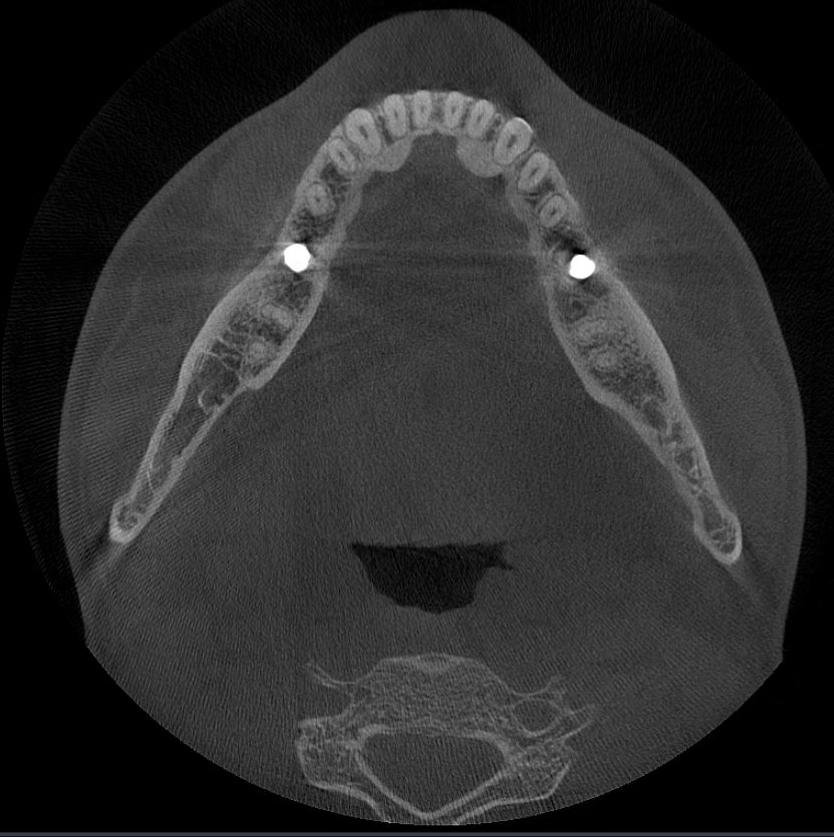

Các hiện vật kim loại được xóa bằng công nghệ AI và cấu trúc răng, mão kim loại và cấy ghép được phục hồi chính xác dựa trên các nguyên tắc toán học.

MAR mới